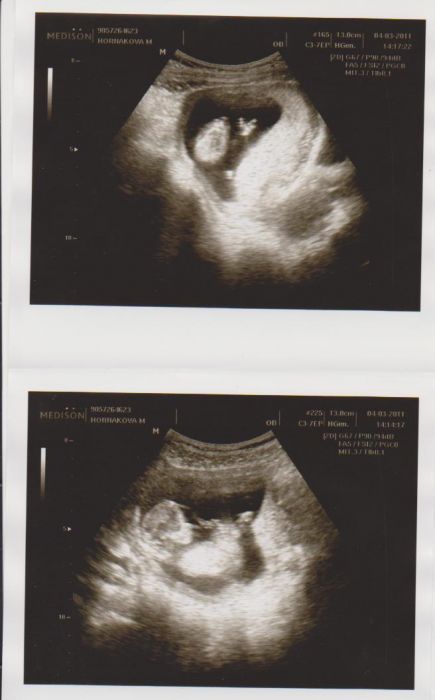

Tak ještě než půjdu spát. Mně vždy fascinuje, jak tady pečlivě přepočítávají prstíčky a ukazují: tady jedna ledvina a tady druhá ... No když to řekne, tak tam prsty vidím, ale na té noze fakt nevim, jestli jich bylo pět, nebo jen 4. Ale budu mu věřit

Táta se mu pokoušel vysvětlit, že to pan doktor povolil, ale nějak to nezabralo, prostě máma je nemožná a neumí se zout. Miminko nebylo vidět moc dobře, ale snad to i malej pochopil. Máme portrét, celá se už na obrázek samozřejmně nevejde. Kdybychom měli obrázek z minula, tak už ho dělat nebudem, ale minule se potvůrka schovávala.